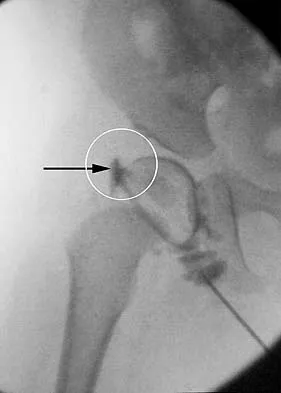

Figure 36 shows the hip arthrogram of a newborn. Which of the following structures is enclosed by the circle?

Explanation

The structure enclosed by the circle is the acetabular labrum. It is visible as the white point of tissue outlined by the darkly radiopaque contrast. The appearance of the contrast surrounding the sharp white point of a normal labrum is called the "rose thorn sign." The limbus is the term reserved for a rounded, infolded labrum seen with arthrography. The pulvinar is the fatty tissue seen in the empty acetabulum when the hip is dislocated. The ligamentum teres is seen as a white stripe outlined by contrast coursing from the central acetabulum to the dislocated femoral head. The transverse acetabular ligament courses across the inferior portion of the acetabulum and is not clearly seen with arthrography. Herring JA: Tachdjian's Pediatric Orthopaedics, ed 3. Philadelphia, PA, WB Saunders, 2002, vol 1, pp 532-533.